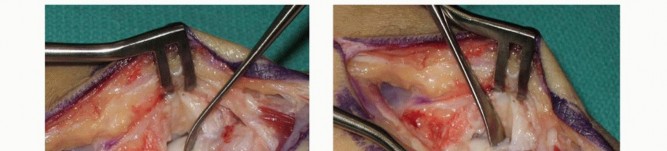

The execution of the volar wedge bone grafting technique requires absolute precision. We begin with a curvilinear incision over the volar aspect of the wrist. The incision starts proximally over the flexor carpi radialis (FCR) tendon, approximately 3-4 cm proximal to the wrist crease, and extends distally, gently curving across the wrist flexion creases to terminate at the base of the thenar eminence, safely avoiding the palmar cutaneous branch of the median nerve.

Image

Superficial dissection is carried down through the subcutaneous tissue to identify the FCR tendon sheath. Using a #15 blade, the superficial fascia of the FCR sheath is incised longitudinally. The FCR tendon is then mobilized and retracted radially. Deep to the FCR, the surgeon will encounter the floor of the tendon sheath, which is sharply divided. At this juncture, the volar superficial branch of the radial artery is frequently encountered traversing the field; it is carefully isolated, ligated, and divided to prevent troublesome bleeding and to allow unimpeded access to the deep carpal structures.

Deep dissection requires meticulous protection of the neurovascular structures. The median nerve and the digital flexor tendons are gently retracted ulnarly using a blunt Wheatlander or a Ragnell retractor. The deep volar radiocarpal capsule is now exposed. A longitudinal or H-shaped capsulotomy is performed over the scaphoid. It is a critical surgical pearl to preserve the integrity of the long radiolunate (LRL) ligament and the proximal portion of the radioscaphocapitate (RSC) ligament to prevent iatrogenic destabilization of the proximal pole. The capsular flaps are tagged with fine sutures for later repair.

With the capsule open, the scaphoid nonunion site is brought into direct view. The nonunion is often obscured by fibrous scar tissue and a pseudarthrosis. Using a combination of a sharp dental pick, small curettes, and a high-speed burr, the fibrous tissue is meticulously debrided. The sclerotic bone ends of both the proximal and distal fragments must be resected back to healthy, bleeding, cancellous bone. The appearance of punctate bleeding—the "paprika sign"—confirms the viability of the fragments. Once debrided, the true extent of the volar bone void and the humpback deformity becomes glaringly apparent.